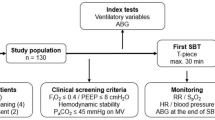

Adult candidates for extubation were divided into a training set (n = 38) to determine threshold values of indices for assessing extubation and a prospective validation set (n = 59) to determine the predictive power of the threshold values for patients successfully extubated and those who failed extubation. All were evaluated for extubation during a spontaneous breathing trial (5 cmH2O pressure support ventilation, 5 cmH2O positive end expiratory pressure) using routine clinical practice standards. WOBN/min data were blinded to attending physicians. Area under the receiver operating characteristic curves (AUC), sensitivity, specificity, and positive and negative predictive values of all extubation indices were determined.

In this IRB-approved study, a waiver of informed consent was granted to record breathing pattern and related data in 97 adults (Table 1) in a surgical ICU at a university medical center who were considered candidates for extubation based on routinely used inclusion and exclusion criteria (Table 2). Patients had received ventilatory support for 9 ± 3 days (Model 840 ventilator, Puritan Bennett, Pleasanton, CA). The first 38 or approximately 40% of patients were designated as a training set to determine threshold values for indices that best differentiated patients who were successfully extubated (n = 31) or who failed extubation (n = 7), a 22% failure rate. The predictive power of the threshold values for each index was assessed in the subsequent 59 or 60% of patients in a prospective validation set who were successfully extubated (n = 47) or who failed extubation (n = 12), a 25% failure rate. The reported incidence of extubation failure ranges between 6 and 47% [14]. Failure rates for our two patient sets are comparable and near the middle of this range.

As routinely used, a spontaneous breathing trial (SBT) of PSV 5 cmH20 with PEEP 5 cmH2O (FIO2 ≤ 0.40) was performed with sedation/analgesia temporarily removed or reduced to obtain a Riker Sedation-Agitation Score of 4 [15]. During the SBT all indices were measured after 30 and 90 min; measurements at 90 min were used for statistical analysis. An arterial blood gas was obtained 5 min prior to and 30 min after extubation. The decision to extubate was made by the attending physician based on routinely used criteria (Table 2). For both patient sets and during all phases of the study, WOBN/min data were blinded to attending physicians and did not influence the decision to extubate. Following extubation, all patients breathed spontaneously through an aerosol facemask (FIO2 0.40). Successful extubation was defined using routine standards as the ability to sustain appropriate spontaneous breathing (f ≤ 30/min) and blood gas exchange, i.e., pulse oximeter oxygen saturation (SpO2) > 92%, PaO2/FIO2 ≥ 150–300, PaCO2 ≤ 50 mmHg for non-chronic obstructive pulmonary disease (COPD) patients, ≤55–60 mmHg for COPD patients, pH ≥ 7.30, and ability to cough and protect airway for greater than 24 h after extubation. Objective criteria for extubation failure were PaCO2 > 50 mmHg for non-COPD patients and >55–60 mmHg for COPD patients, PaO2 < 60 mmHg (FIO2 ≤ 0.40), f > 35/min, inability to cough and/or protect airway, and a worsening of hemodynamic or neurological conditions. Patients failing extubation were reintubated and provided with ventilatory support at the direction of the attending physician.

A combined pressure/flow/carbon dioxide sensor, positioned between the endotracheal tube and Y piece of the ventilator breathing circuit, directed data to a respiratory monitor (NICO, Respironics) for measurements including PSV, PEEP, f, V T, f/V T, MV, inspiratory flow rate, partial pressure end-tidal CO2 (PetCO2), SpO2, CO2 min production (VCO2), and physiologic dead space volume-to-tidal volume ratio (V D/V T). All data from the monitor were, in turn, directed to a laptop computer containing software (Convergent Engineering, Gainesville, FL) for calculating respiratory system compliance (Crs) and resistance (Rrs) using the least squares method [16], and operating an ANN to determine WOBN/min. The training of this ANN and validation of WOBN/min data compared to conventional measurements of work of breathing per minute using an esophageal balloon in a similar group of adults receiving PSV have been described [10].

ROC curves for non-invasively determined work of breathing per min (WOBN/min) in J/min and some traditional indices used to predict extubation from ventilatory support such as spontaneous breathing frequency in breaths/min (f), spontaneous tidal volume in ml (V T), and the ratio of spontaneous breathing frequency to tidal volume or index of rapid shallow breathing (f/V T) in breaths/min/l are shown for the prospective validation set of patients. The area under the curve (AUC) is generated by plotting the true positive rate or sensitivity against the false-positive rate or 1-specificity. AUC for WOBN/min was significantly greater (i.e., a better model for predicting) than AUCs for f, V T, and f/V T ratio, as well as other indices used to predict extubation, as shown in Table 4 (p < 0.05)